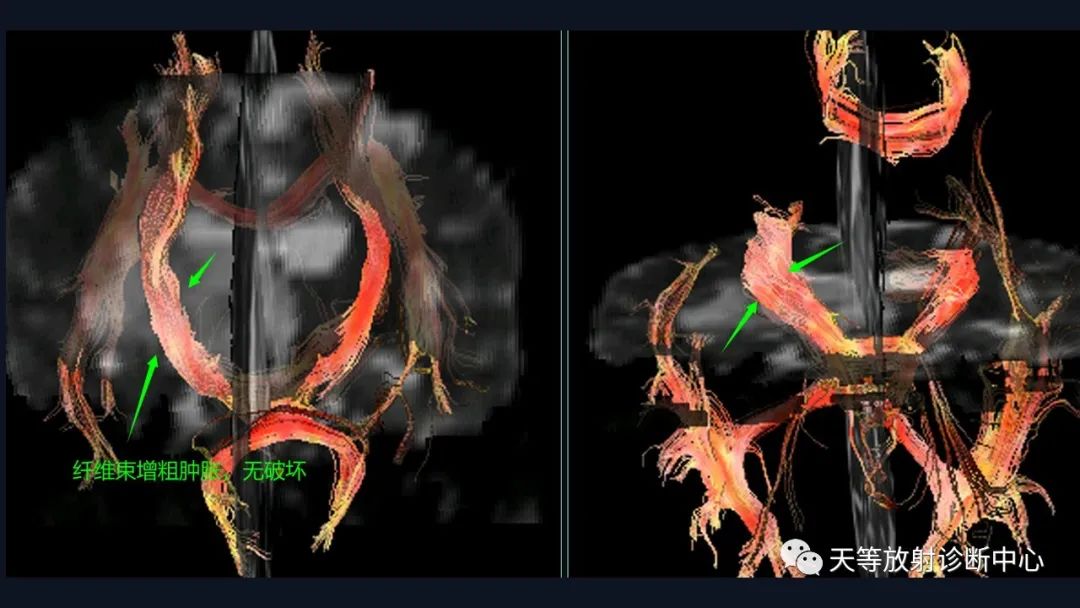

本病例影像学特点:

脑内占位的特点:

1、刀切征

2、凹陷征或肚脐凹征

3、尖角征

4、多发

5、DWI呈稍高信号

6、形态上怪异

6、NAA及Cho减低,出现导致LL峰。

结合颈部、胸廓入口区及腋窝多发淋巴结肿大并相互融合。

综合考虑淋巴瘤